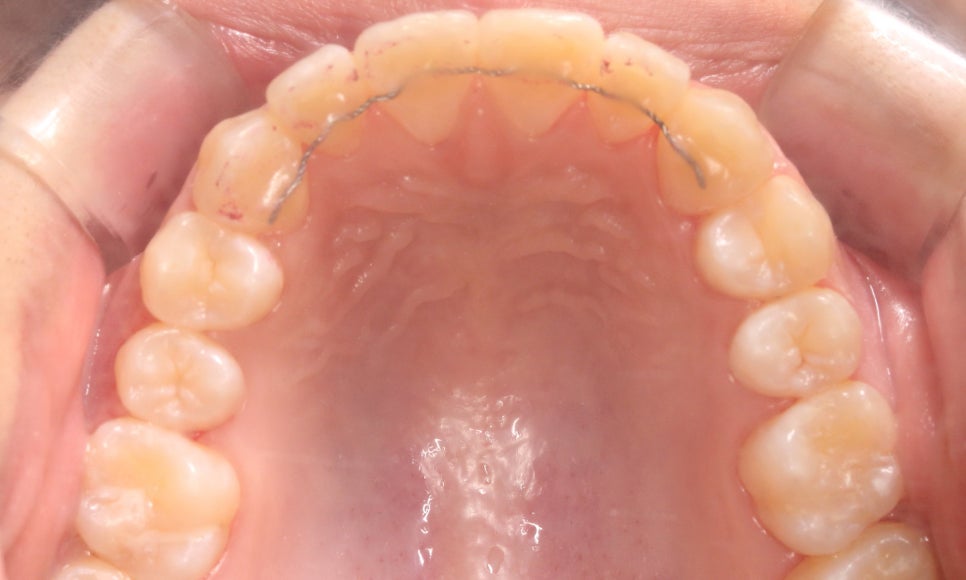

윗니의 안쪽 면을 보면

작은 앞니(측절치)의 크기가

주변 치아보다 확실히 작은 모습인데요,

아랫니를 보시면

왜소치가 아님에도 치아 끝이

톱니처럼 울퉁불퉁한 것을 확인할 수 있습니다!